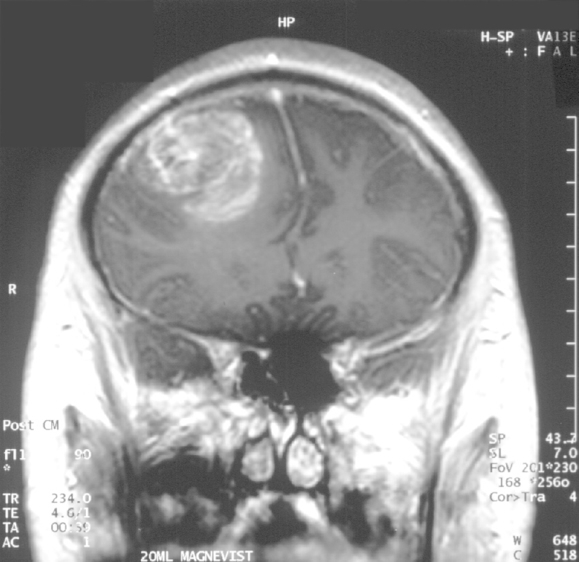

3. Glioblastoma Multiforme (GBM)

- Origin: High-grade astrocyte tumour

- Macro: Supratentorial, solid with possible cysts

- Features:

- Rapid progression, severe headache, seizures

- Personality changes, hemiparesis

- Treatment: Palliative (surgery + chemo/radiotherapy + corticosteroids)

- Prognosis: Poor (<1 year median survival)